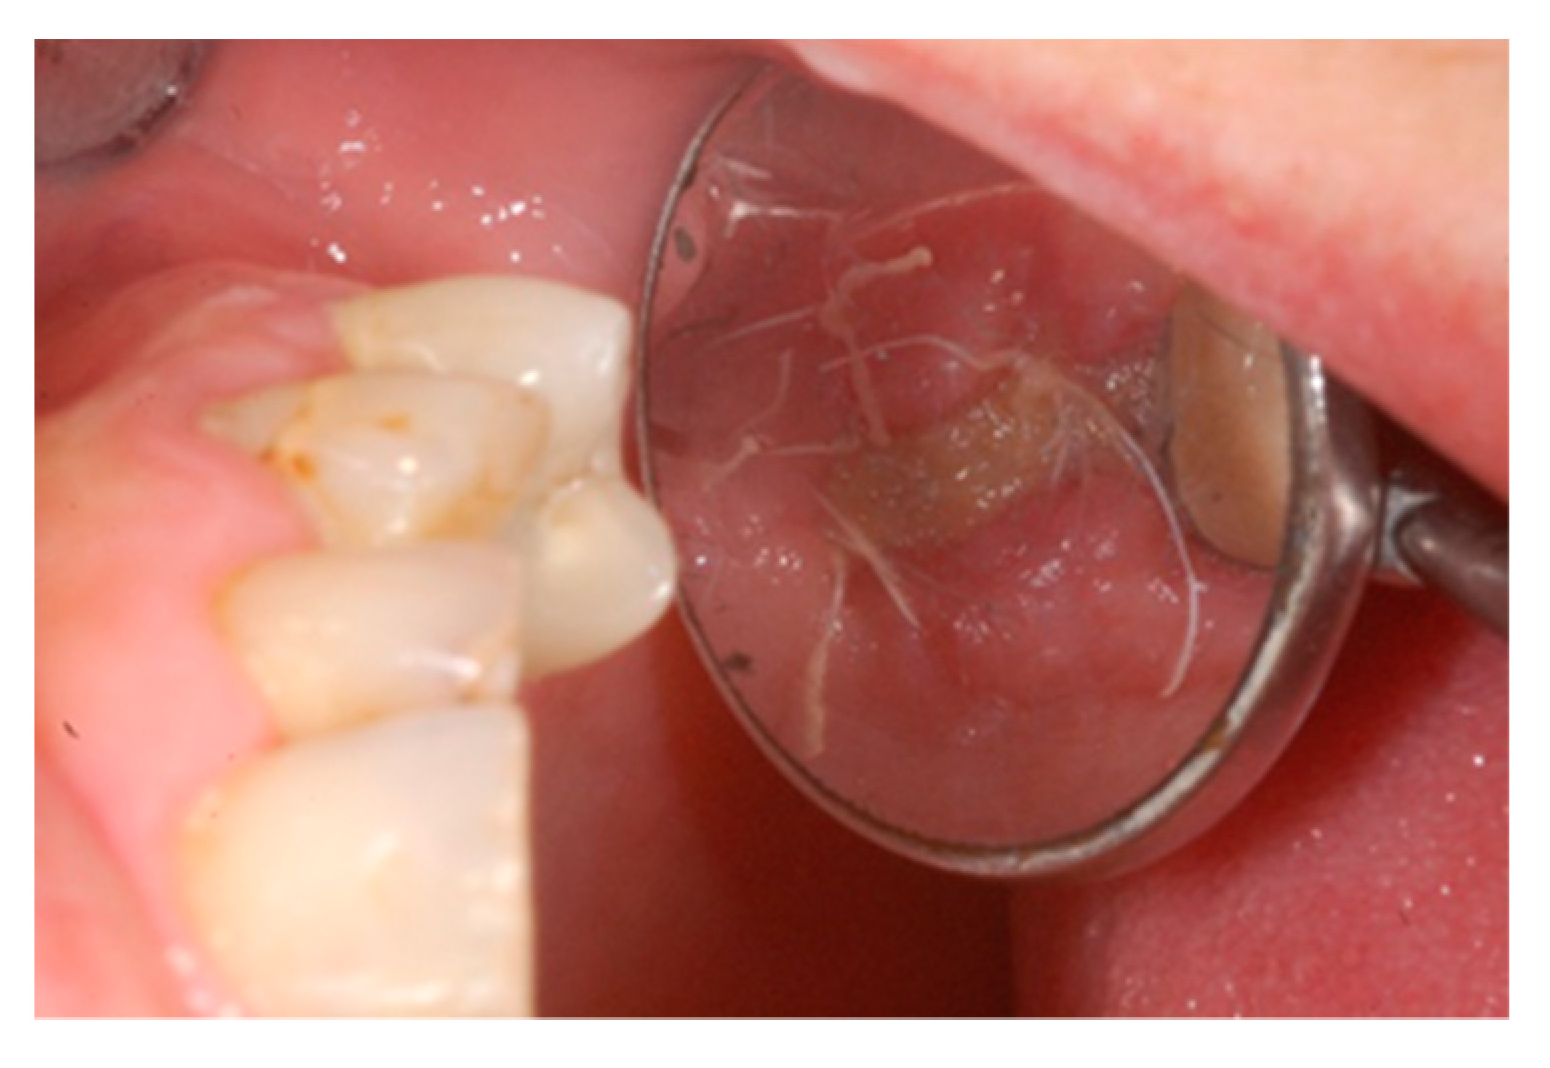

The one-month recall showed a full coverage of the site by epithelialized tissue, thus, indicating perfect healing (Figure 8).

Figure 8.

Intraoperative view of the oral mucosa at one month post tooth extraction. Soft tissues appeared to be completely healed with no signs of bone exposition, considered as a clear sign of BRONJ.